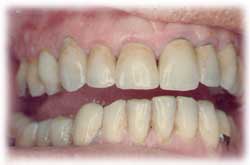

- Podrá hablar, reír y sonreír sin

preocuparse por sus nuevos dientes : están firmemente anclados y los sentirá

igual que si fueran sus propios dientes.

- Recuperará su sonrisa natural.

Los implantes dentales nos permitirán masticar con total comodidad, sonreír y hablar con la misma seguridad que con nuestros propios dientes.